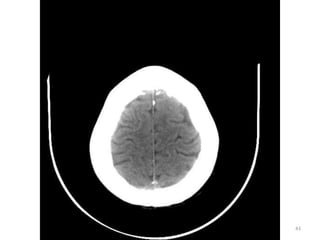

1. Fissura de Sylvios.

2. Foice do cérebro.

3. Terceiro ventrículo.

39

1. Corno Anterior do

Ventrículo lateral D.

2. Corpo caloso D.

4. Plexo coróide.

40